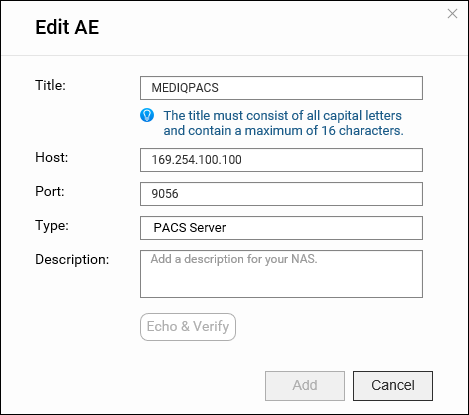

应用实体 (AE) 管理

在 DICOM 中,应用实体 (AE) 表示 DICOM 网络中的端点系统或程序,例如设备或 PACS 服务器。将 NAS 配置为 PACS 服务器时,将它视为一种 AE。

在 MediQPACS 的“AE Management”(AE 管理)屏幕中,用户可以在本地或外部网络上添加、编辑、删除、搜索和测试其他 AE 的连接。

编辑 AE